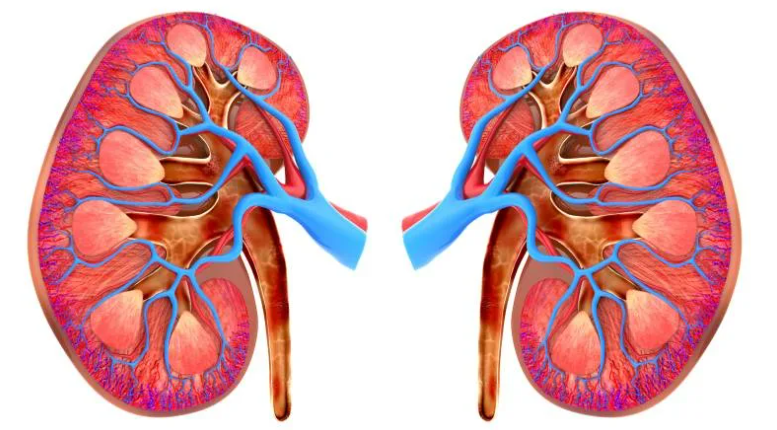

Dowamly piýelonefrit

Böwrek ýetmezçiligi

Peşew daş keseli

Nefrotiki sindrom

Böwrek, simptomatiki gipertoniýa

Dogabitdi we nesilden geçyän böwrek...

Çagalarda Tubulopatiýa keseli